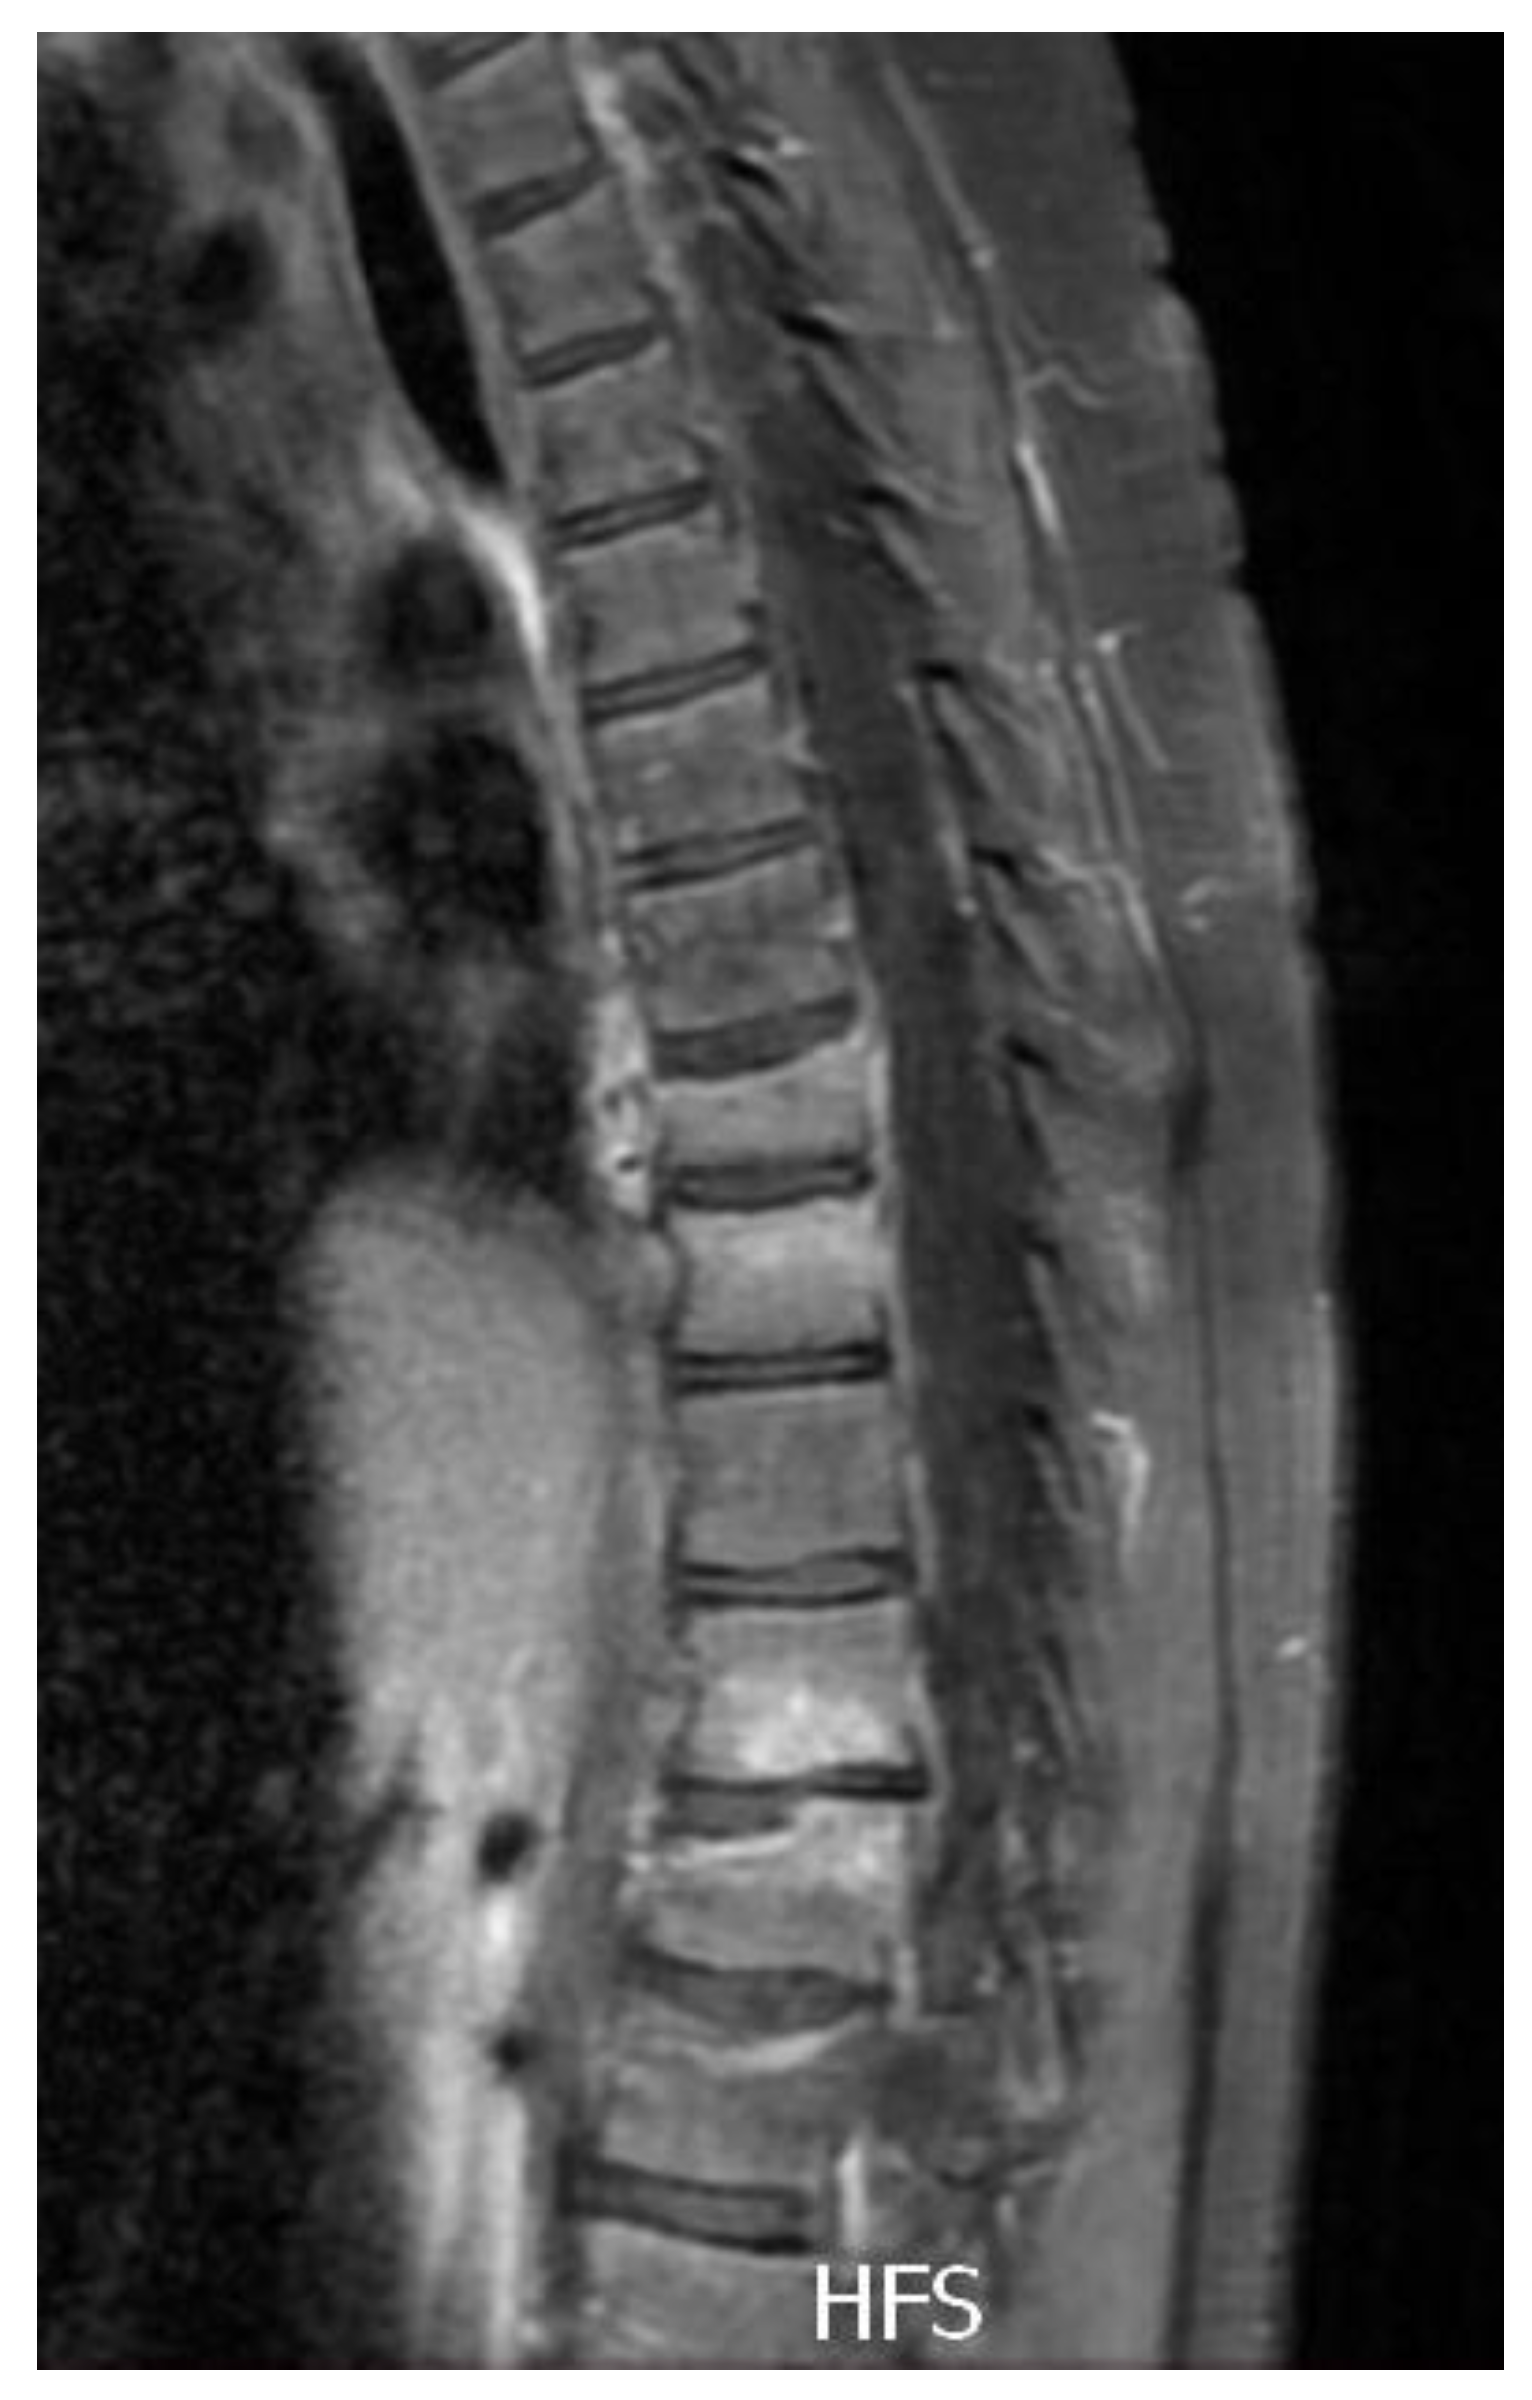

2.3. Diagnostic Assessment

2.4. Therapeutic Intervention

2.5. Follow-Up and Outcomes